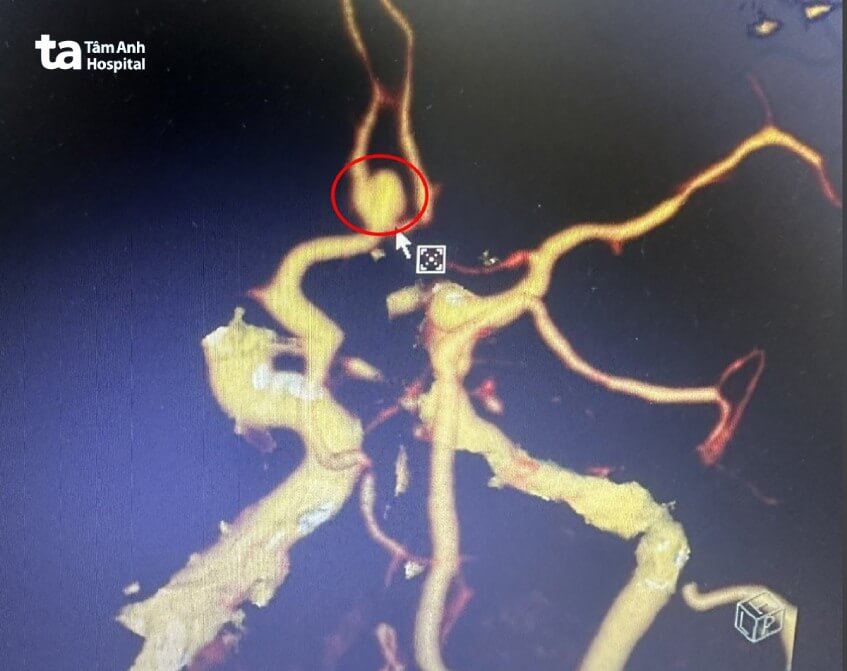

Ngay lập tức, bệnh nhân được chỉ định chụp mạch máu não (CTA). Kết quả cho thấy có một túi phình động mạch thông trước (vị trí nối 2 động mạch não trước), kích thước gần 1 cm. Túi phình bị vỡ gây xuất huyết dưới nhện tự phát (chảy máu ở các khoang màng nhện) và xuất huyết vùng bể trên yên.

Các bác sĩ hội chẩn, chỉ định phẫu thuật kẹp, loại bỏ túi phình. Mục đích ngăn ngừa nguy cơ tái vỡ, bảo tồn tất cả những động mạch xung quanh, kể cả động mạch mang túi phình.